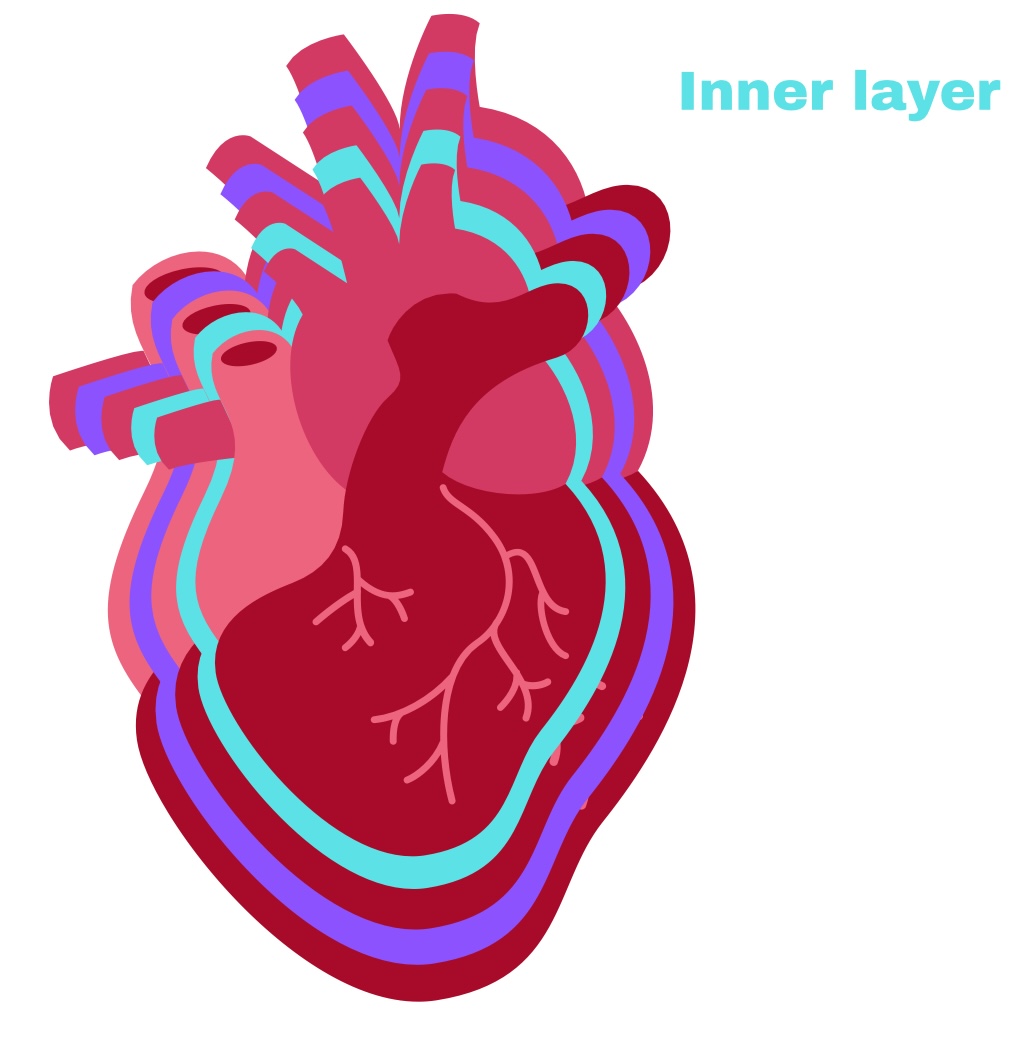

Partial Pericardium

Outer layer

Visceral Pericardium

Deep layer (surface of organ)